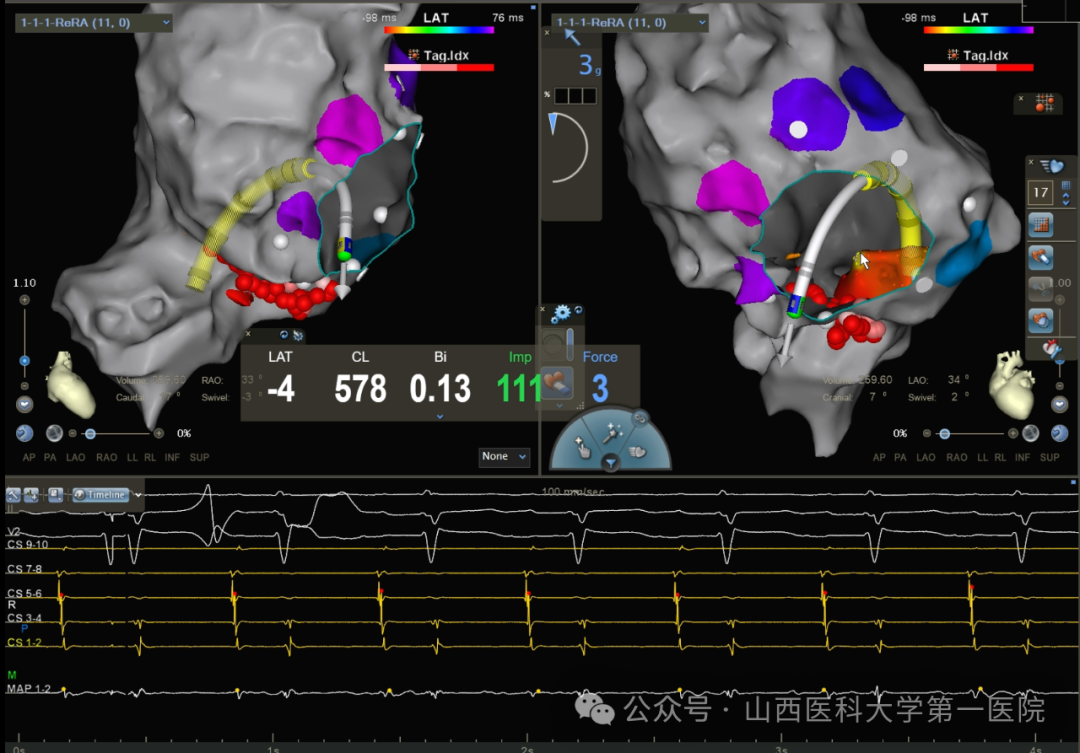

更换Vizigo鞘管进行三尖瓣峡部消融,房扑周长逐渐延长至240-250ms,直至房扑终止。在ICE指引下,导管配合可调弯鞘管行倒U法贴靠,对游离壁侧补充消融,验证CS口和右房游离壁底部双向传导阻滞,起搏冠状窦口下沿三尖瓣环标测,传导顺序符合峡部线阻滞情况,心房Burst 刺激未诱发心动过速。观察20min后重复电生理检查结果同前,手术结束术后心电图示窦性心律。

通常情况,消融三峡至下腔静脉时,会直至导管头端不能记录到电位或者观察到导管跨过欧式嵴后出现头端的滑落判断是否达到下腔静脉口附近,进而停止消融。有的患者需要回撤消融导管才可见到欧式嵴和三尖瓣环之间的三尖瓣峡部,部分患者可见到与欧式嵴相连接的欧式瓣,最后通过顺时针或者逆时针旋转消融导管选择相对平整的峡部(偏向游离壁侧或间隔侧)进行线性消融。(本例偏向游离壁侧进行了巩固消融)